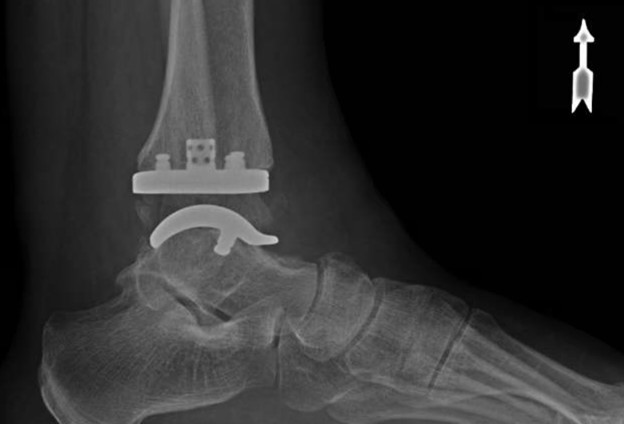

Led by Dr. Vinod Panchbhavi, a world-renowned orthopaedic foot and ankle surgeon, our fellowship covers all aspects of foot and ankle surgery including trauma, reconstruction, ligament and tendon injuries, arthroscopy, arthroplasty, and midfoot and

where he performed around 100 cases of total ankle arthroplasty. His other clinical interests include minimally invasive surgery and foot and ankle trauma.